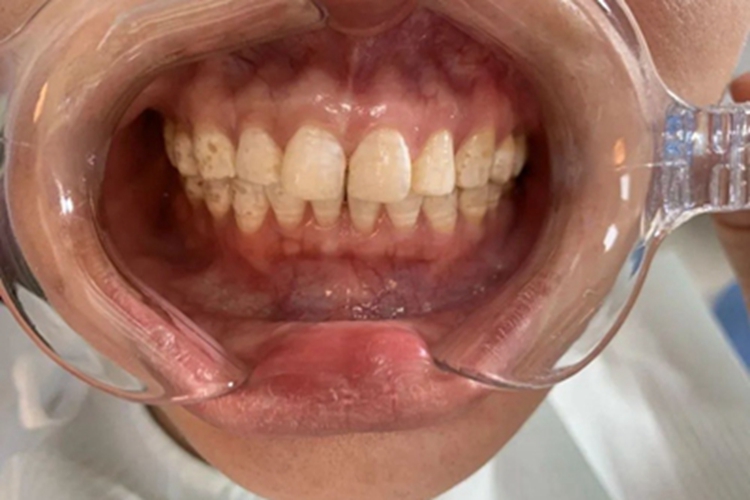

氟斑牙可导致牙齿出现异常的变色,表面有色素沉积,形成点状、片状的浅黄色、黄褐色的斑点,大小不一、数量不等,形状并不规则,并且分布也无具体规律。斑点可与周围平齐,也可呈凹陷状稍低于周围,但是不会对牙齿的完整性产生破坏。

氟斑牙患者牙齿表面有异常的斑点时,可遵医嘱使用过氧化氢、稀盐酸等进行药物脱色,消除牙齿表面的不规则斑块。此外,日常需注意保持口腔卫生,注意饮食,减少氟牙磨损。